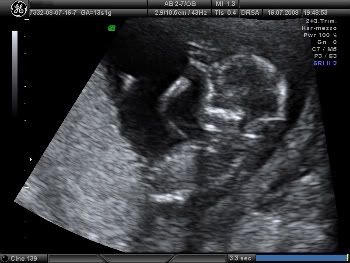

Un terzo figlio :-) Tiziano

And the winner is....your mother's son (but not one of your bros).

Complimenti -Ecco la foto promessa:

E' lungo-a 7,36 cm e dovrebbe arrivare il 21 gennaio.